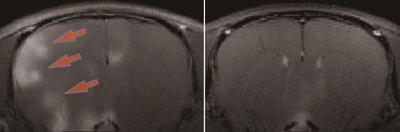

研究面では、医療情報学ユニットと連携し、磁気共鳴医学および画像情報学の手法を中心に、神経生理学および脳神経科学の分野で、ヒトおよび実験動物 を対象に研究を行っています。近年の医療画像技術の発展は、疾病の早期発見など臨床面に多大なる貢献をするとともに、脳機能や神経生理学の研究にも革命的 な変化をもたらしました。医療情報学ユニットでは、国内有数の設備を誇る磁気共鳴画像装置を使用して、1)鍼灸刺激をはじめとする体性感覚刺激に伴う脳機 能の解析、2)筋の運動に伴う代謝の解析や収縮や変形に伴う筋の生理学的な変化を捉える研究、3)脳神経疾患の病態評価および治療効果の評価、および4) 神経生理学および脳神経科学に有用な新技術の開発など、ヒトおよび動物モデルを対象に研究を進めています。図1は右手合谷に電気刺激を行ったときのヒトの 脳機能画像;fMRI., 図2は右手合谷に温熱刺激を行ったときのfMRIを示す。神経活動に伴って生じる血液の酸素代謝の変化と血流の変化を反映しています。図3は通電刺激を 行ったときのラットの神経賦活画像;AIM MRI。神経活動に伴って生じるカルシウムの動きに合わせて、神経の内部に蓄積した造影剤の変化を捉えています。

図2. 合谷に温熱刺激を与えたときの脳の賦活部位 |